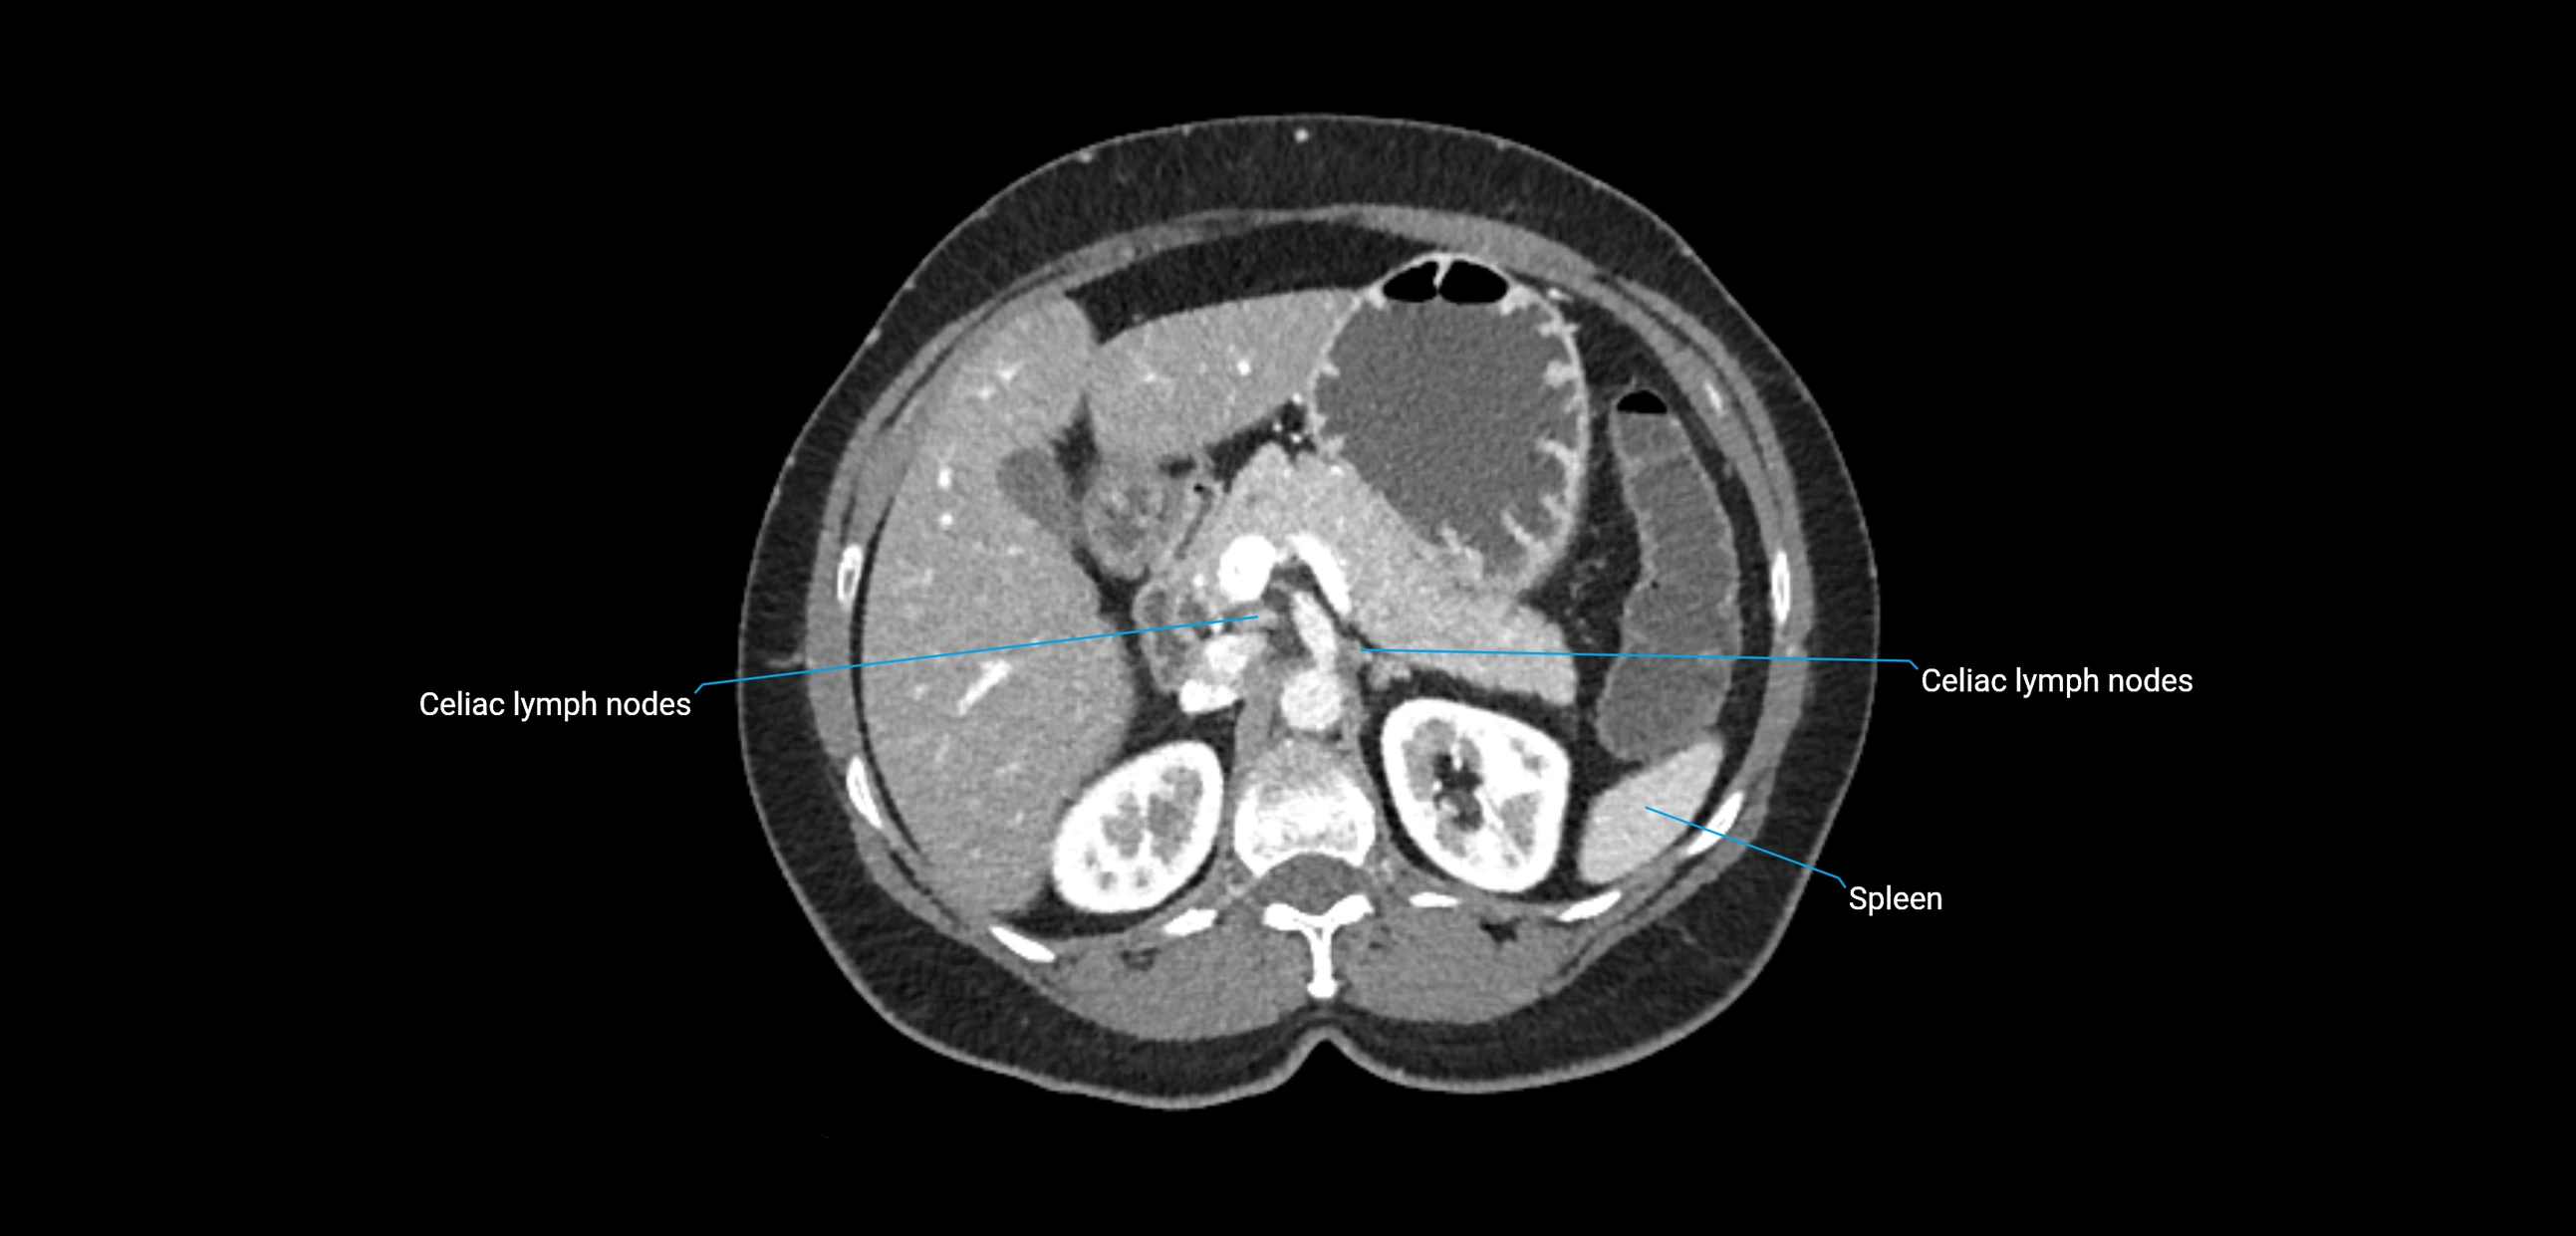

CT Appearance

CT Pre-Contrast:

• Nodes appear as soft-tissue density nodules adjacent to the aorta and IVC

• Calcification may be seen in chronic infections (e.g., tuberculosis)

CT Post-Contrast:

• Normal nodes enhance homogeneously

• Malignant nodes may show heterogeneous enhancement, central necrosis, or conglomerate formation

• Size >1 cm short axis is suspicious, though morphology and distribution are equally important